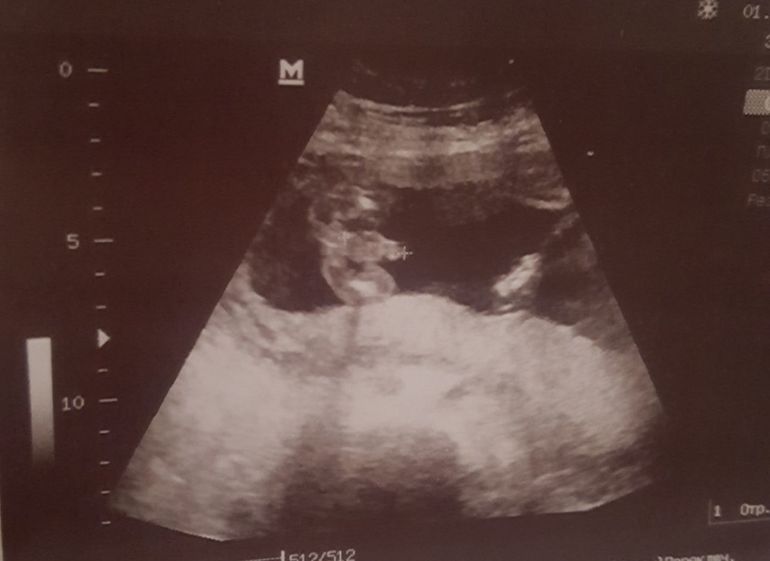

Страхи, переживания и немножечко нытьяСегодня с утра сбегала на узи т.к. пару дней беспокоили тянущие боли во влагалище, почитала об этом и стало страшно, что это может быть укорачивается шейка.. но оказалось что зря боялась и все хорошо там у моего пупсика) активно шевелится, на неделю опережает срок и шейка целых 5см, хотя была 4,2) ну и конечно узистка посчитала своим долгом напечатать нашему папе(к 8 марта🤣как она сказала) фоточку с писюльком нашего сыночка)))